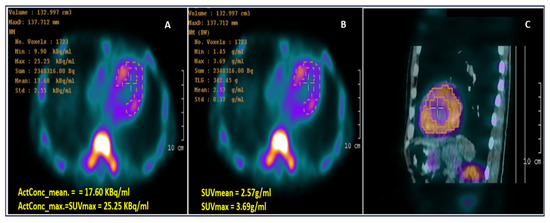

Objectives: Doxorubicin, a widely used chemotherapeutic agent, is known to induce hepatotoxicity through oxidative stress and inflammatory pathways. Vitamin D has been reported to exert antioxidant and immunomodulatory effects; however, its potential protective role in doxorubicin-induced liver injury remains insufficiently characterized. Materials and Methods: Adult male Wistar albino rats were randomly assigned to six groups (n = 7): Control, Vitamin D (5000 IU/kg), Vitamin D (60,000 IU/kg), Doxorubicin, DOX + Vitamin D (5000 IU/kg), and DOX + Vitamin D (60,000 IU/kg). Vitamin D3 (cholecalciferol) was administered orally either as a daily dose (5000 IU/kg for 12 days) or as a single bolus dose (60,000 IU/kg). Doxorubicin (6 mg/kg/day, cumulative dose 18 mg/kg) was administered intraperitoneally on days 10–12. Hepatic injury was evaluated using 99mTc-pyrophosphate (99mTc-PYP) scintigraphy, serum liver enzymes (AST, ALT, LDH, total bilirubin), renal markers (BUN, creatinine), calcium and 25-hydroxyvitamin D [25(OH)D], oxidative stress parameters (MDA, TOS, TAS, GSH, SOD, Nrf2), and inflammatory cytokines (TNF-α, IL-6, IL-1β, IL-10). Results: Doxorubicin markedly increased hepatic 99mTc-PYP uptake and significantly elevated AST, ALT, LDH, bilirubin, MDA, TOS, TNF-α, IL-6, and IL-1β levels while reducing Nrf2, GSH, SOD, TAS, and IL-10 (all p < 0.001). Vitamin D supplementation significantly increased serum 25-hydroxyvitamin D [25(OH)D] levels compared with controls (32.3 ± 2.7 vs. 74.1 ± 3.8 and 69.3 ± 3.2 ng/mL for the 5000 and 60,000 IU/kg groups, respectively; p < 0.001) and attenuated DOX-induced hepatic injury, as indicated by reduced radiotracer uptake and improved oxidative and inflammatory markers. Vitamin D also mitigated DOX-associated increases in renal injury markers (BUN and creatinine) without inducing hypercalcemia. No significant differences were observed between the two vitamin D dosing regimens in most outcome measures. Conclusion: Vitamin D supplementation exerted protective effects against doxorubicin-induced liver injury, likely through modulation of oxidative stress and inflammatory pathways. Additionally, 99mTc-PYP scintigraphy may serve as a useful imaging tool for detecting acute hepatocellular injury and evaluating therapeutic responses. Full article